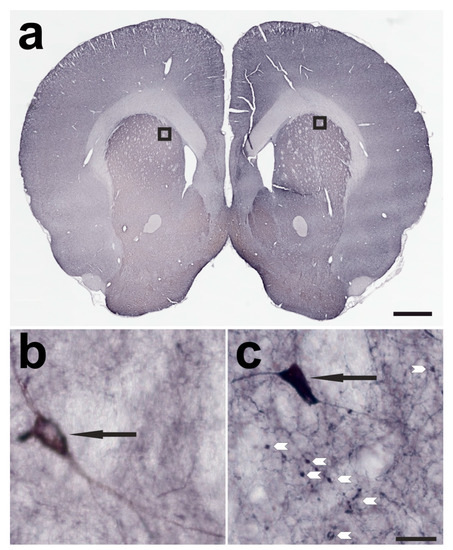

2.1. Verification of Successful BoNT-A Injection—Botulinum Neurotoxin-A-Induced Varicosities

4.4. Tissue Preparation and Histochemistry